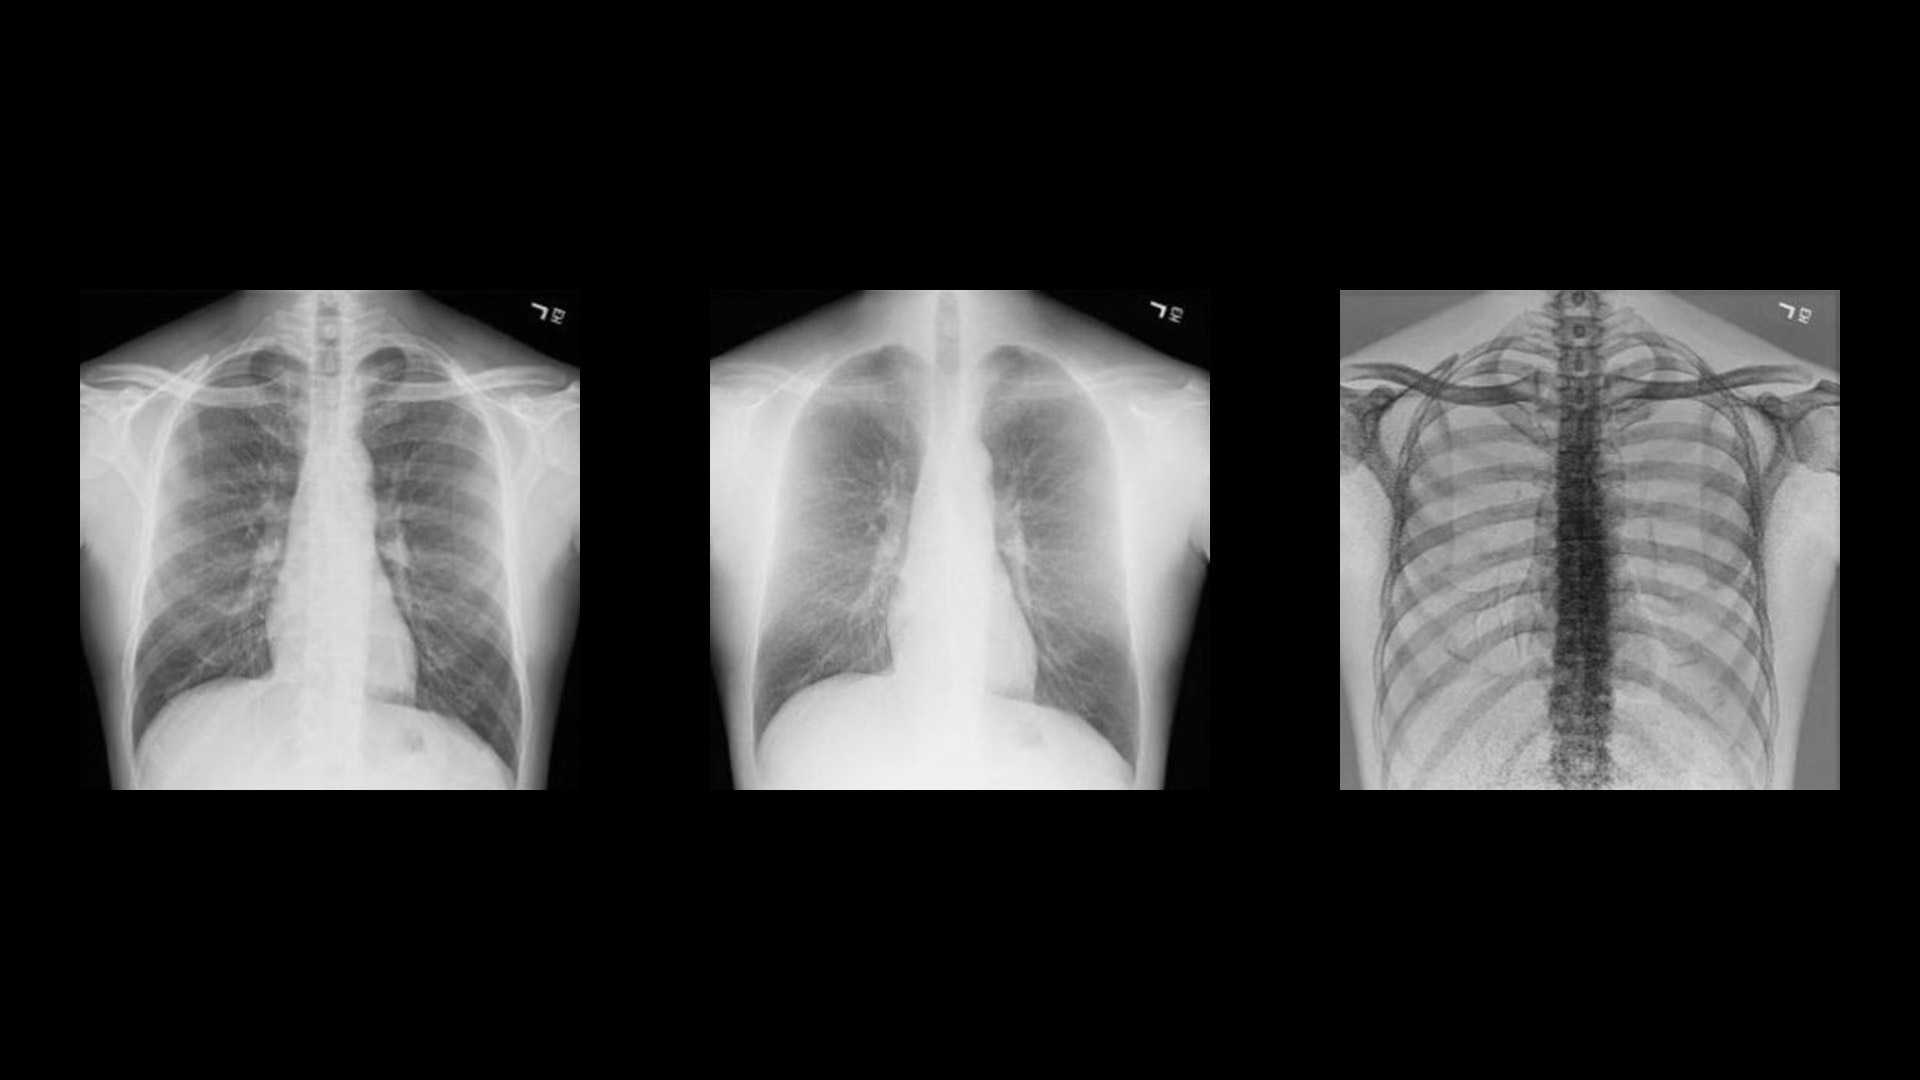

Rather than relying solely on algorithmic image processing, Dual Energy Subtraction acquires two exposures at different energy levels in less than 160 milliseconds. You can process and view the image as:

• A standard radiographic image

• An image with bones subtracted

• An image of just the bones to highlight foreign objects or calcified structures

These images help you detect abnormalities that may have been obscured in a conventional radiograph.